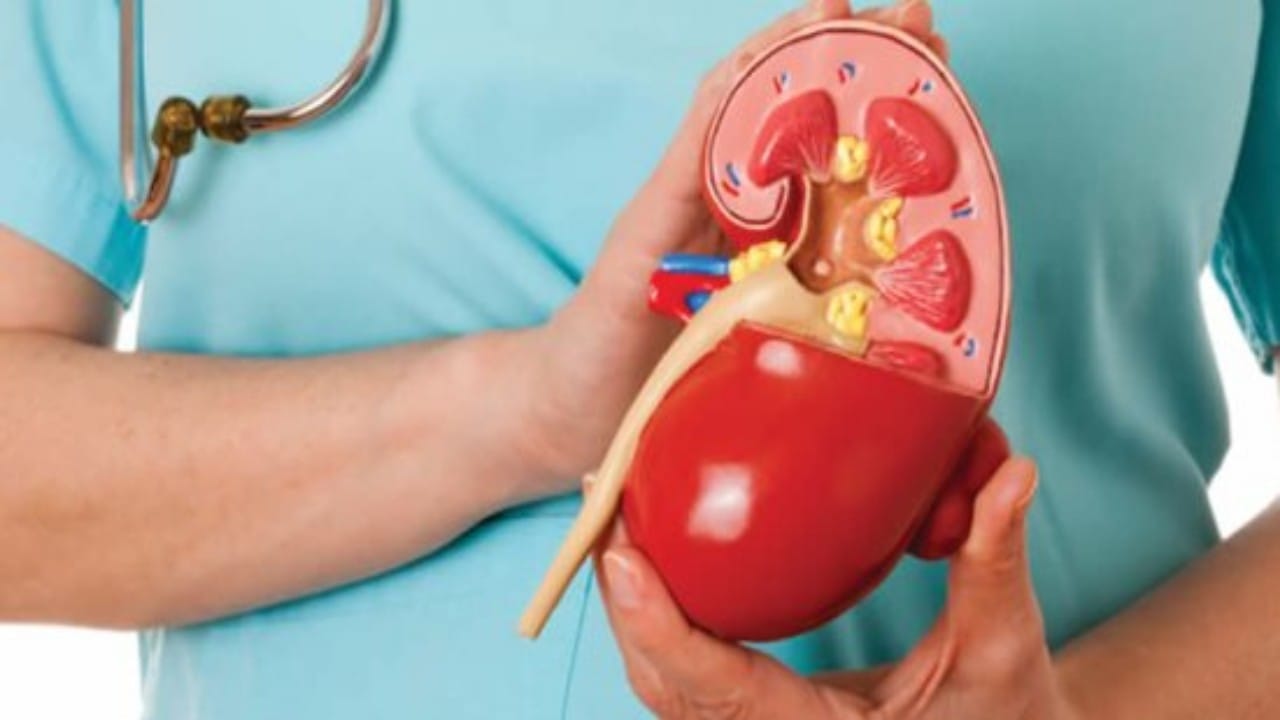

أمراض الكلى

استشاري : زواج الأقارب ينتج عنه الإصابة بأمراض الكلى .. فيديو

سبب إصابة النساء بأمراض الكلى بعد الثلاثين

نصائح هامة للوقاية من أمراض الكلى

دراسة تكشف تأثير تناول المأكولات البحرية على صحة الكلى

أبرزها خشونة البشرة.. 8 علامات تشير إلى الإصابة بأمراض الكلى

“استشاري”: السكري هو السبب الرئيسي لتلف الكليتين

استشاري: 70% من أسباب الفشل الكلوي هي داء السكري وارتفاع ضغط الدم

أنواع أمراض الكلى